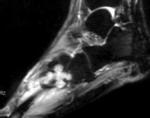

Пролиферативный синовит характеризуется появлением большого количества выпота. Обычно патология дает о себе знать из-за тяжелых травм, но может развиться из-за инфекции или чрезмерных нагрузках на сустав. В большинстве случаев болезнь протекает хронически. При длительном течении возникает утолщение синовиальной оболочки. Необходимо как можно скорее снять отечность и не допустить появления фиброзных изменений в суставной капсуле.

Пигментный виллёзонодулярный синовит - редкое заболевание с доброкачественным течением, характеризующееся пролиферативными изменениями синовиальной оболочки, отложением гемосидерина, образованием ворсинок, паннуса. Две разновидности: виллёзонодулярный бурсит и виллёзонодулярный тендосиновит. Частота - 2 на I 000 000. Преобладающий возраст • Виллёзонодулярный бурсит - 30-40 лет • Виллёзонодулярный тендосиновит -50-60 лет. Преобладающий пол - женский. Этиология. В 30% случаев развитию синовита предшествует травма сустава. Патоморфология. Пролиферация клеток синовиальных оболочек с образованием узлов, содержащих клеточный инфильтрат из фибробластов, лимфоцитов, макрофагов с жировыми включениями. Клиническая картина • Виллёзонодулярный бурсит -моноартрит. Чаще всего (80% случаев) поражается коленный сустав, реже - (с убывающей частотой) тазобедренный, голеностопный и плечевой суставы • Виллёзонодулярный тендосиновит - образование узелков в мышечных сухожилиях и связках сустава. Лабораторные исследования • Увеличение СОЭ • Синовиальная жидкость ксантохромная, с примесью крови • Биопсия синовиальной оболочки: узловая пролиферация, гемосидероз, инфильтрация мононуклеарными клетками. Рентгенологическое исследование • Остеопороз и наличие остеофитов нехарактерны • Артропневмография: множественные округлые дефекты наполнения синовиальной полости, обусловленные наличием узлов или гипертрофированных ворсинок синовиальной оболочки • МРТ - выявление гемосидерина и жировых включений. Артроскопия • Суставной хрящ приобретает коричневую окраску вследствие гемосидероза • Различной величины узлы коричневого цвета. Дифференциальный диагноз • Виллёзонодулярный бурсит • Липома - в аспиратах отсутствует ксантохромная жидкость • Остеоартроз - кисты возникают только на суставных поверхностях, подвергающихся нагрузке, тогда как при пигментном виллёзонодулярном синовите они образуются на всех суставных поверхностях. Остеофи-ты, напротив, более типичны для остеоартроза • Воспалительные арт-ропатии, дебютирующие моноартритом, - ревматоидный артрит, туберкулёзный артрит, анкилозирующий спондилоартрит и др. • Виллёзонодулярный тендосиновит - панглии (околосухожильные кисты): аспираты ганглиев содержат гелеподобную жидкость. Лечение хирургическое • Виллёзонодулярный бурсит • Тотальное иссечение синовиальной оболочки, вероятность рецидива заболевания составляет 25-40% • Лучевая терапия • Виллёзонодулярный тендосиновит - иссечение кист. Синоним. Синовит геморрагический МКБ. М12.2 Ворсинчато-узелковый (виллонодулярный) синовит (пигментный)

Пигментированный ворсинчато-узловой синовит (ПВУС) - пролиферативно-диспластическое поражение синовиальных оболочек суставов, слизистых сумок и сухожильных влагалищ. Обычно поражаются крупные суставы, особенно коленный. Синонимы: пигментированный ворсинчато-узловой синовит, пигментный вилонодулярный синовит, миелоксантома, гигантоклеточный синовит, фиброзная синовиальная ксантома, полиморфно-клеточная опухоль синовиальных оболочек, гигантоклеточная доброкачественная опухоль синовиального влагалища. Имеются данные, позволяющие предполагать связь заболевания с местным нарушением липидного обмена.

Диагностика данной патологии, за редким исключением, возможна только при диагностической артроскопии с последующей биопсией. Артроскопическая картина во всех рассмотренных случаях довольно характерна. Синовиальная оболочка отечна и утолщена. Почти на всем ее протяжении, особенно в верхнем завороте, покрыта резко гипертрофированными, отечными синовиальными ворсинами. Формы их весьма разнообразны, но превалируют ветвистые и полипообразные, которые наиболее часто располагаются в области задней стенки верхнего заворота на передней поверхности бедренной кости. Характерной особенностью является то, что синовиальная оболочка окрашивается в различные оттенки буровато-коричневого цвета. Нередко наблюдаются также поверхностные фибринозные наслоения. Некоторые авторы отмечают возможную инвазию патологически измененной синовиальной оболочки на суставной хрящ.